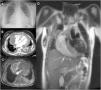

Paciente de 19 años con dolor centrotorácico y disnea progresiva reciente de grado II (NYHA). Inicialmente se constató cardiomegalia (fig. 1A), aumento de LDH y dímero D. Ante la sospecha de tromboembolia pulmonar, se realizó una tomografía computarizada (fig. 1B) que mostró una gran masa tumoral mediastínica con captación heterogénea de contraste y compresión de cavidades derechas. En una resonancia magnética con gadolinio (fig. 1C,D) se observó que la masa no tenía plano de separación con la aurícula derecha. Una mediastinoscopia diagnóstica posterior permitió el diagnóstico de angiosarcoma cardiaco. Para evaluar la extensión de la enfermedad, se solicitó una tomografía por emisión de positrones con 18F-FDG (fig. 2A: PET y B: PET-TC) que mostró hipermetabolismo cardiaco de predominio derecho con extensión pericárdica (fig. 2C), alguna adenopatía perilesional (fig. 2D) y 2 lesiones hipermetabólicas focales hepáticas (probables metástasis; fig. 2E), junto a derrame pleural derecho masivo. Estos hallazgos descartaron la posibilidad de rescate quirúrgico y se inició tratamiento sistémico con taxanos, doxorrubicina por lo que terapia de soporte. Pese a todo, la paciente falleció transcurridos 7 meses a consecuencia de fallo cardiaco compresivo.

La incidencia del angiosarcoma cardiaco es extremadamente baja. Se debe considerar la cirugía de resección o trasplante en todos los pacientes. Entre los estudios de imagen la PET 18F-FDG permite identificar alteraciones metabólicas que pueden preceder a las lesiones estructurales visualizadas con técnicas radiológicas. En nuestro caso, contribuyó a evaluar la agresividad tumoral y su extensión sistémica, lo que repercutió directamente en las opciones terapéuticas.